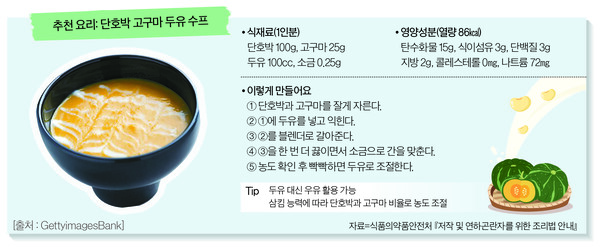

식후 목소리 변하면 병원가세요…뇌가 보내는 ‘위험 신호’

노인 3명 중 1명 겪는 삼킴장애